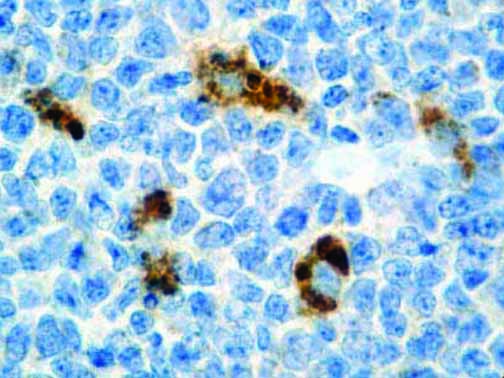

It is the ICU physician who is most likely to witness one of the deadliest manifestations of the abnormal immunological response, the cytokine storm syndrome (CSS). This response is also referred to by some as the cytokine release syndrome (CRS). CSS is characterized by continuous activation and expansion of macrophage and lymphocyte populations, which secrete large amounts of cytokines, causing the cytokine storm. This massive cytokine release is akin to hemophagocytic lymphohistiocytosis (HLH) disease, a syndrome characterized by initial unchecked and persistent activation of cytotoxic T lymphocytes and NK cells.

Clinical and laboratory manifestations of HLH include fever, enlarged liver and/or spleen, neurologic dysfunction, coagulopathy, liver dysfunction, cytopenias (i.e., low levels of erythrocytes, leukocytes, and/or platelets), hypertriglyceridemia, hyperferritinemia, hemophagocytosis, and eventually diminished NK cell activity as the immune system becomes progressively paralyzed. HLH can be familial (primary HLH) or secondary to another disease process (sHLH), such as rheumatic disease, in which it is referred to as macrophage activation syndrome (MAS, characterized by elevated ferritin).